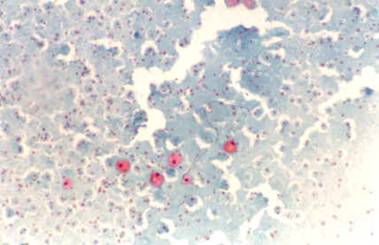

Barbat de 57 ani. Tiroida de dimensiun marite, de consistenta mult marita, dureroasa la palpare, cu suprafata neregulata cu senzatie de nodularitate. Ecografia: cresterea volumului; marginile lobilor rau definite; structura este intens neomogena cu alternanta de arii hipoecogene de edem si altele intens ecogene, cu aspect pseudonodular. Examene de laborator: moderat hipertiroidism; indici de fibroza mult ridicati. Citoaspiratie -celule gigante de tip Langhans, celule inflamatorii de tip acut si cronic, numerosi fibroblasti.

Examen citologic

Acelasi pacient. Celule gigante polinucleate, linfocite, granulocite si tireocite involuate pe fond bogat coloid.

Papanicolau 2,5 X.